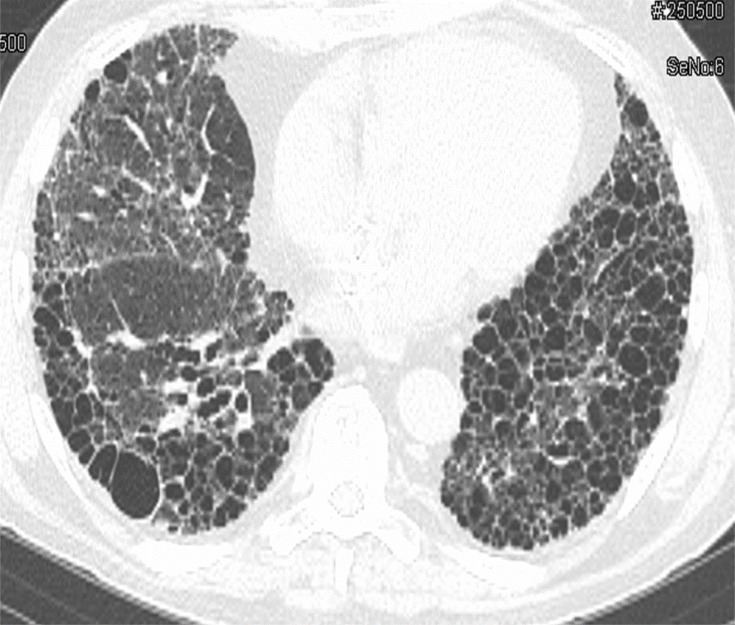

Major subtypes of RA-ILD are defined by their histopathological and/or high-resolution computed tomography (HRCT) patterns. Usual interstitial pneumonia (UIP) (characterized on high-resolution computed tomography (HRCT) by predominantly basal, subpleural, and patchy honeycombing, reticular opacities, and traction bronchiectasis without nodularity, consolidation or extensive ground glass opacities) is the most common subtype,6 and it carries a poor prognosis (Figure 1).7 Nonspecific interstitial pneumonia (NSIP), cryptogenic organizing pneumonia (COP), and acute interstitial pneumonia (AIP) are other subtypes of RA-ILD that are seen with far less frequency than UIP.

Figure 1.

This image shows a slice from a high-resolution computed tomography scan from a 68 year-old man with rheumatoid arthritis-related interstitial lung disease in a pattern of usual interstitial pneumonia. The predominant abnormality is honeycombing marked by side-by-side and stacked honeycomb cysts. The entire visualized portion of the left lung base (right side of image) is destroyed with honeycombing, whereas, the visualized portion of the right lung shows honeycombing situated in its characteristic subplueral region. Other findings include traction bronchi- and bronchiolectasis and reticular opacities.